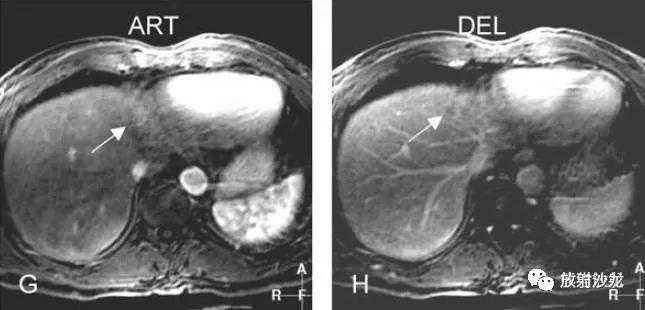

G:动脉期,局部放大图像,大结节强化较明显;

H:延迟期,局部放大图像,大结节并未见肿瘤包膜。